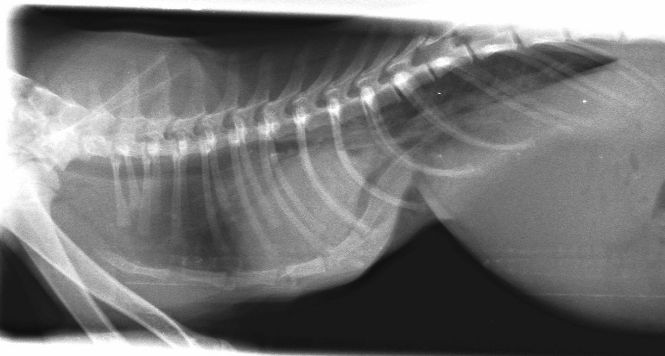

Lateral chest x-ray showing severe pectus deformity – note the dorsal deviation of the caudal sternebrae which is diagnostic for pectus excavatum